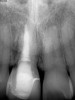

Fig 6. Clinical presentation of patient with a failing tooth No. 8.

Figure 6

Fig 7. Preoperative radiograph showing previous endodontic therapy on tooth No. 8.

Figure 7

Plugging into digital workflows provides opportunities to integrate CAD/CAM technologies at every step of the treatment process for dental implants. In another example, a patient presented with a failing tooth No. 8 (Figure 6 and Figure 7). After discussing treatment options, the patient chose to forgo any treatment to address tooth and soft-tissue asymmetries and wanted to proceed with a dental implant-supported restoration without additional treatment. After integrated 3-dimensional planning, the tooth was extracted, and then an implant and the final custom CAD/CAM abutment (titanium base with zirconia supra-structure) were placed with a provisional restoration in the same visit (Figure 8 and Figure 9). Soft-tissue grafting was also done at the same visit to address the deficient buccal tissue height on No. 8 (Figure 10). At 3 months, the patient presented for the final restoration, with excellent healing around the implant (Figure 11) and soft-tissue healing guided by the custom abutment (Figure 12).